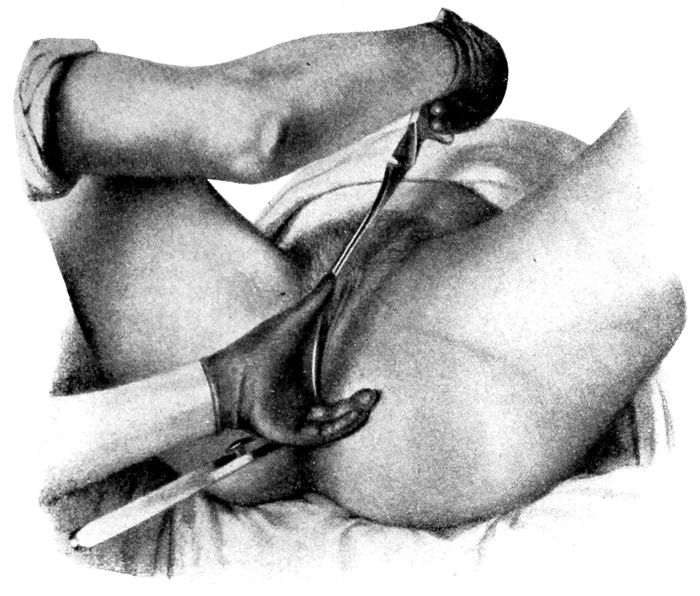

| 80. |

190 |